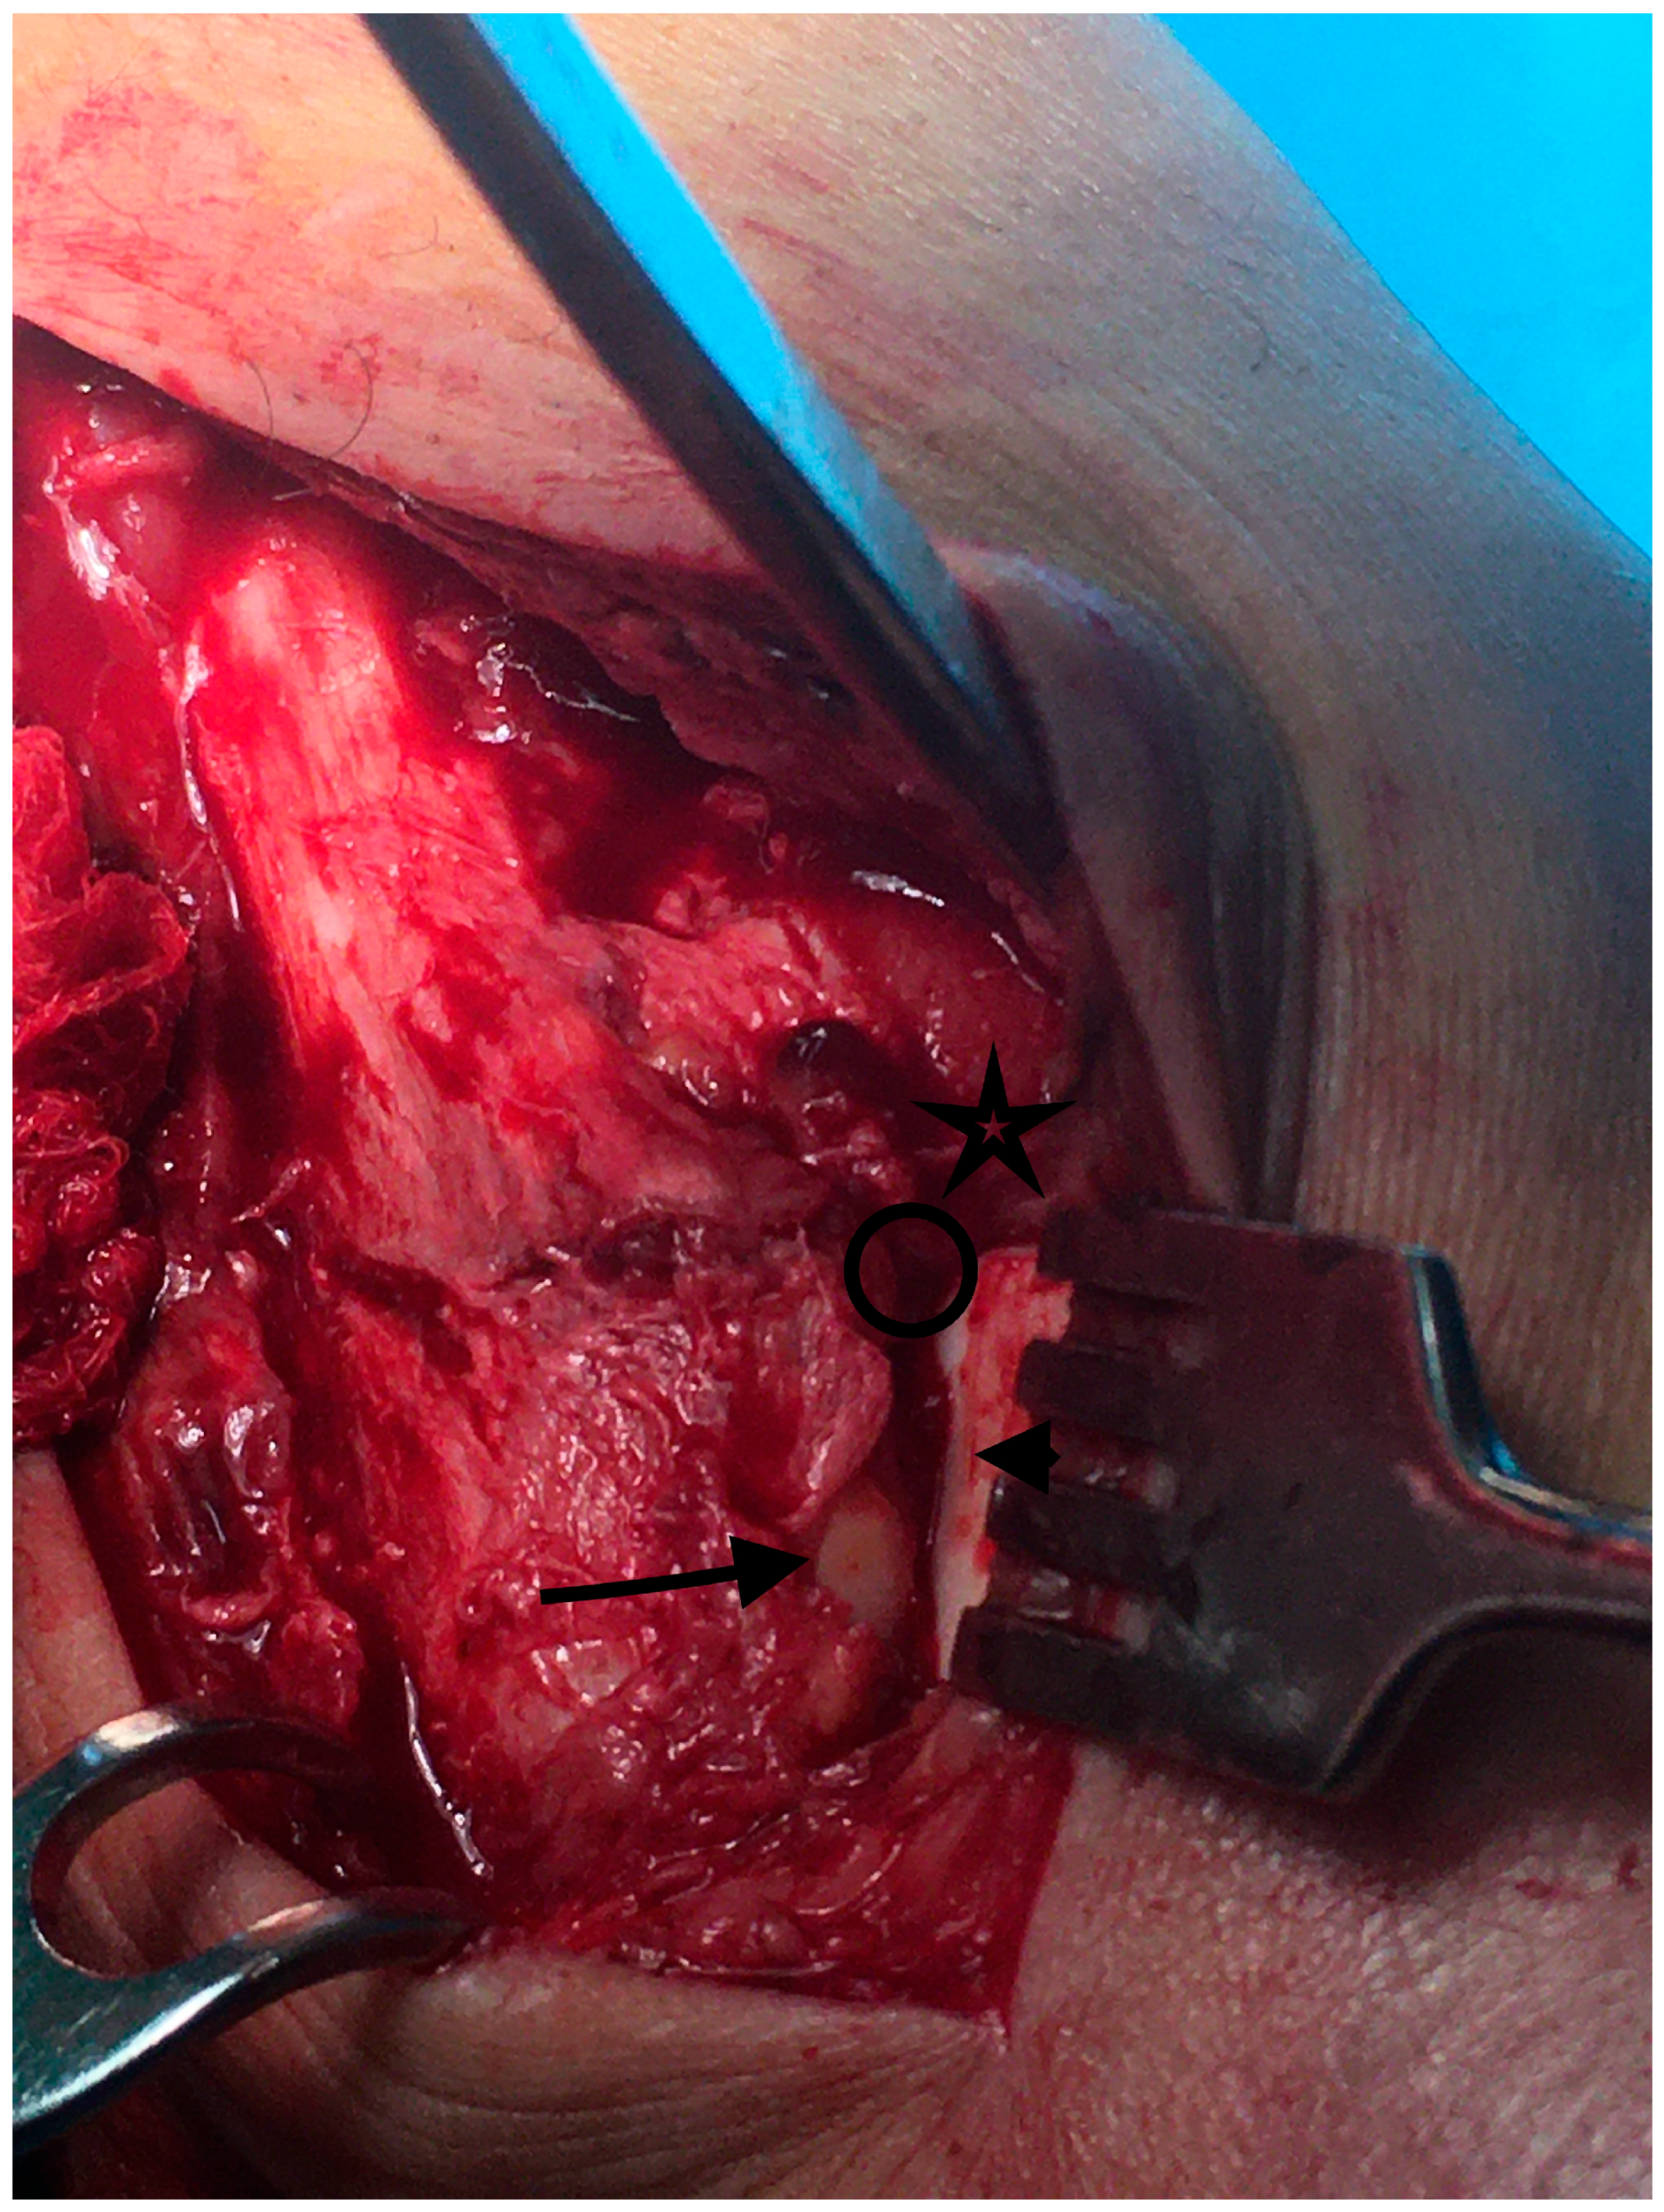

- The superior lateral malleolus cartilage was aligned with the anterolateral tibial plafond cartilage (restoring the fibula length) (Figure 2):

- In the sagittal plane, the lateral malleolus cartilage was fixed as anteriorly as the anterolateral tibial plafond cartilage (restoring the sagittal translation) (Figure 3)